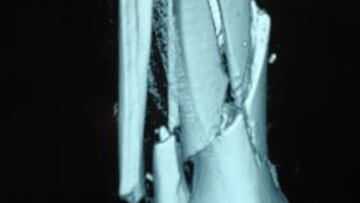

El mejor profesor es el que domina a la perfección la materia que imparte. Por eso, nadie mejor que el doctor Ángel Villamor hablando sobre la cirugía que le ha realizado a Julián Simón, junto a su equipo del Hospital San José, para entender cómo fue la reconstrucción de la tibia y el peroné de la pierna derecha. "La fractura de tibia era de las más complejas que he visto en mi vida, estaba rota en innumerables fragmentos de hueso. En algunos casos se tuvo que realizar la cirugía tras extraer el trozo para atornillarlo y generar la placa de titanio en la mesa de operaciones. No sabemos en cuántos trozos estaba rota, llegamos a tener diez centímetros de tibia sueltos sobre la mesa. En cambio, la de peroné era limpia y no ha dado problemas", explica Villamor.

Por si quedaba alguna duda, el doctor lo resume aún más claro: "La tibia es un tubo de tres caras y estaba tan destruida que en principio no podíamos poner tornillos ya que se aplastaban unos con otros. Por eso tuvimos que ir haciendo pequeñas placas para luego sujetarlo con una placa de titanio de treinta y tantos centímetros que sujetara la tibia entera".